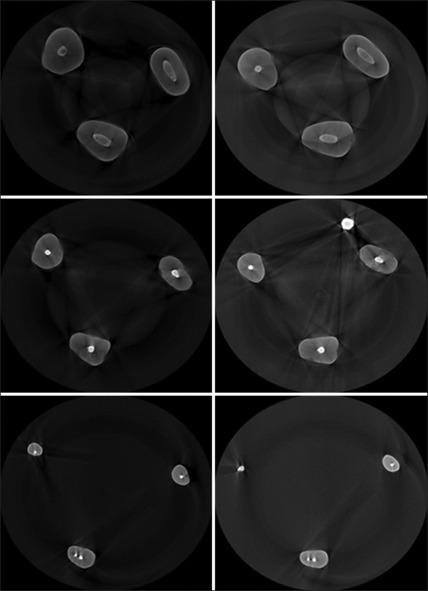

Materials and methods: In this ex vivo quasi-experimental study, 24 single-canal premolars extracted from humans were cleaned and shaped with a motorized and rotary file, then that is divided into two groups. The teeth of each group were filled with gutta F3 and each type of sealant. The teeth were scanned by a micro-computed tomography device after 24 h. After 7 days of storage in phosphate-buffered saline solution, the samples were re-scanned. Data were analyzed using SPSS software (version 21). Descriptive data were presented as frequency, percentage, mean, and standard deviation. The Shapiro-Wilk and Kolmogorov-Smirnov tests were used to investigate the normality of the data. The Mann-Whitney test was used to compare the two groups, and the differences were ultimately not significant. The level of significance was set at 0.05 (P < 0.05).

Results: The mean differences between sealer volumes before and after the intervention were not significantly different between the two groups indicating that the EndoSeal MTA sealer is not inferior to the gold-standard root canal sealer, AHP.